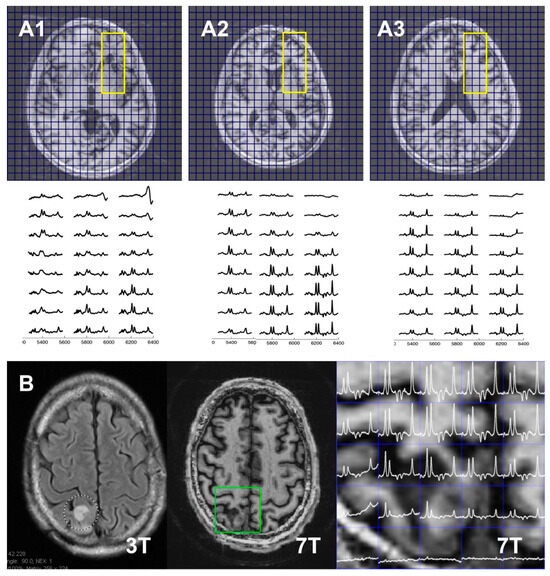

Figure 5 shows data from four-slice Hadamard-encoded moderate-TE spin echo RSI acquisitions in two tumor patients. Both patients had similar clinical histories, including a 5-to-10-year history of treatment and surveillance of a grade 2 oligodendroglioma. The data shown in Figure 5(A1–A3) are from a 47 yrs old tumor patient who was treated 5 years earlier with chemotherapy and external beam therapy. A mild non-enhancing lesion had been seen 2 weeks earlier on a 3T MRI, raising concerns about potential tumor recurrence in the region of the left frontal ventricle and basal ganglia. The 8.8 min scan single-spin-echo moderate-TE four-slice Hadamard study identified elevated Cho and decreased NAA in the area of the forceps minor, which gradually receded superiorly. This was consistent with clinical conclusions of low-grade tumor progression [31,32], with the patient proceeding to additional chemotherapy. Figure 5B shows data from a 69 yrs old patient whose tumor was initially treated 10 years earlier. Low-grade progression was noted 8 years later and again with the present study, with the patient again proceeding to additional chemotherapy.

Figure 5. Moderate-TE spin echo cascaded Hadamard RSI acquisitions from two oligodendroglioma tumor patients, patient #1 (for slice 1 (A1), 2 (A2), and 3 (A3) in the top and middle panels); patient #2 ((B) in the bottom panel). In the (A1A3) top panel, scout T1 anatomy is shown, while in the (B) two left panels, T2 FLAIR at 3T and T1 anatomy at 7T are shown. Spectra were from ROIs (yellow and green rectangle in (A1A3) and (B), respectively). Both patients were clinically identified to have experienced tumor progression, consistent with spectroscopic imaging, although the 69 yo patient #2 shows a more aggressive worsening, with a Ch/NAA ratio of greater than 2 seen at the edge of the brain and lesion.